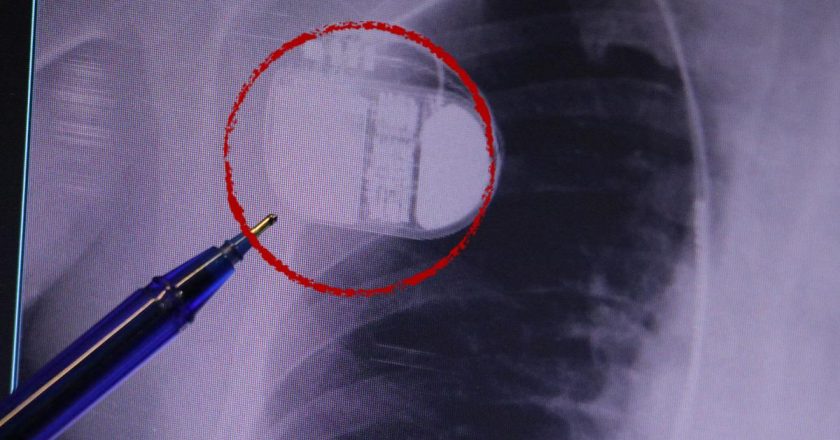

Diyabet tedavisinde devrim niteliğinde yeni bir dönem başlıyor. Diyabet Araştırma Merkezi'nin düzenlediği bilgilendirme toplantısında yapay zeka destekli teknolojilerle geliştirilen 'Yapay Pankreas' sistemleri tanıtıldı. Diyabetin dünya çapında 582 milyon, Türkiye'de ise milyonlarca insanı etkilediğini hatırlatan uzmanlar, bu yeni yöntemlerin hastaların yaşam kalitesini önemli ölçüde artırdığının altını çizdi.